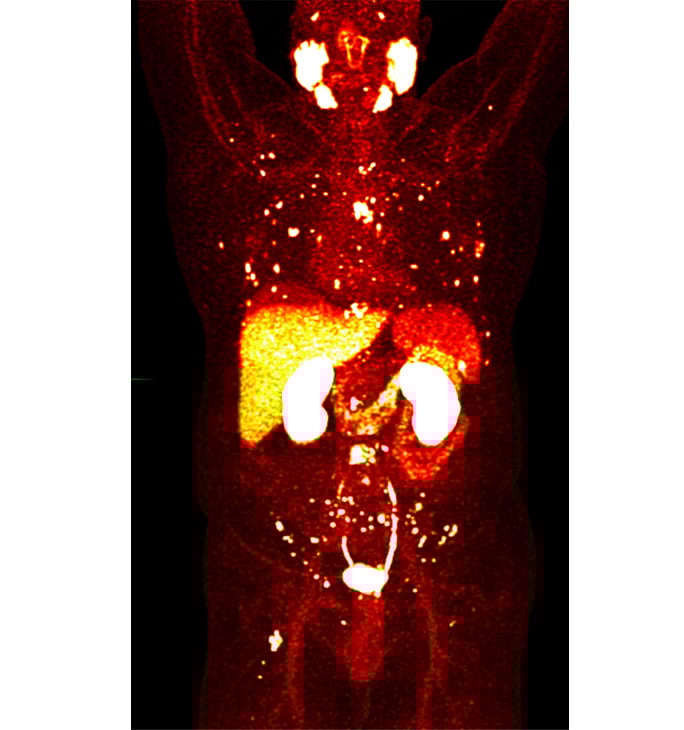

PSMA PET is a diagnostic tool that uses a type of medical imaging called positron emission tomography (PET) to detect prostate cancer anywhere in the body. PSMA stands for prostate specific membrane antigen, a protein found on the surface of prostate cancer cells.

We’ve been using PET imaging to detect cancers for decades. Until recently, however, we haven’t been able to image prostate cancer well because older PET radiotracers – these are radioactive molecules that stick to cancer cells and can be seen on PET scans – do not routinely bind to prostate cancer. However, a new radiotracer, piflufolastat F-18 (also known as 18F-DCFPyL or PyL), does bind to the PSMA on prostate cancer cells. Doctors can look at a PET scan and see if piflufolastat ‘lights up’ prostate cancer cells anywhere in the body.

Today, PSMA PET is the single best method we have to precisely visualize prostate cancer in the body. Knowing the anatomic location of prostate cancer helps us make better treatment decisions and monitor a patient’s response to therapy.

PSMA PET directly targets the tumor on a molecular level to show disease more accurately and at an earlier stage. It easily outperforms conventional imaging; CT, MRI and bone scans cannot match the ability of PSMA PET to find very small tumors.